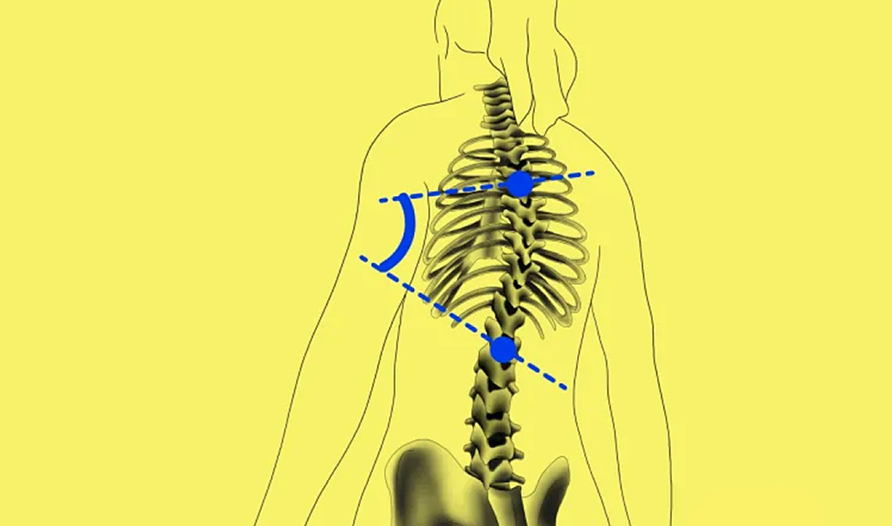

BoneMetrics: Automation of MSK Measurements and Workflow Optimization

With the aid of BoneMetrics, the capture of MSK measurements can be automated. Moreover, workflow optimization can be achieved through unparalleled precision in X-ray and EOS acquisitions.

BoneMetrics automatically performs standard measurements for the feet, legs, pelvis/hips, and spine.